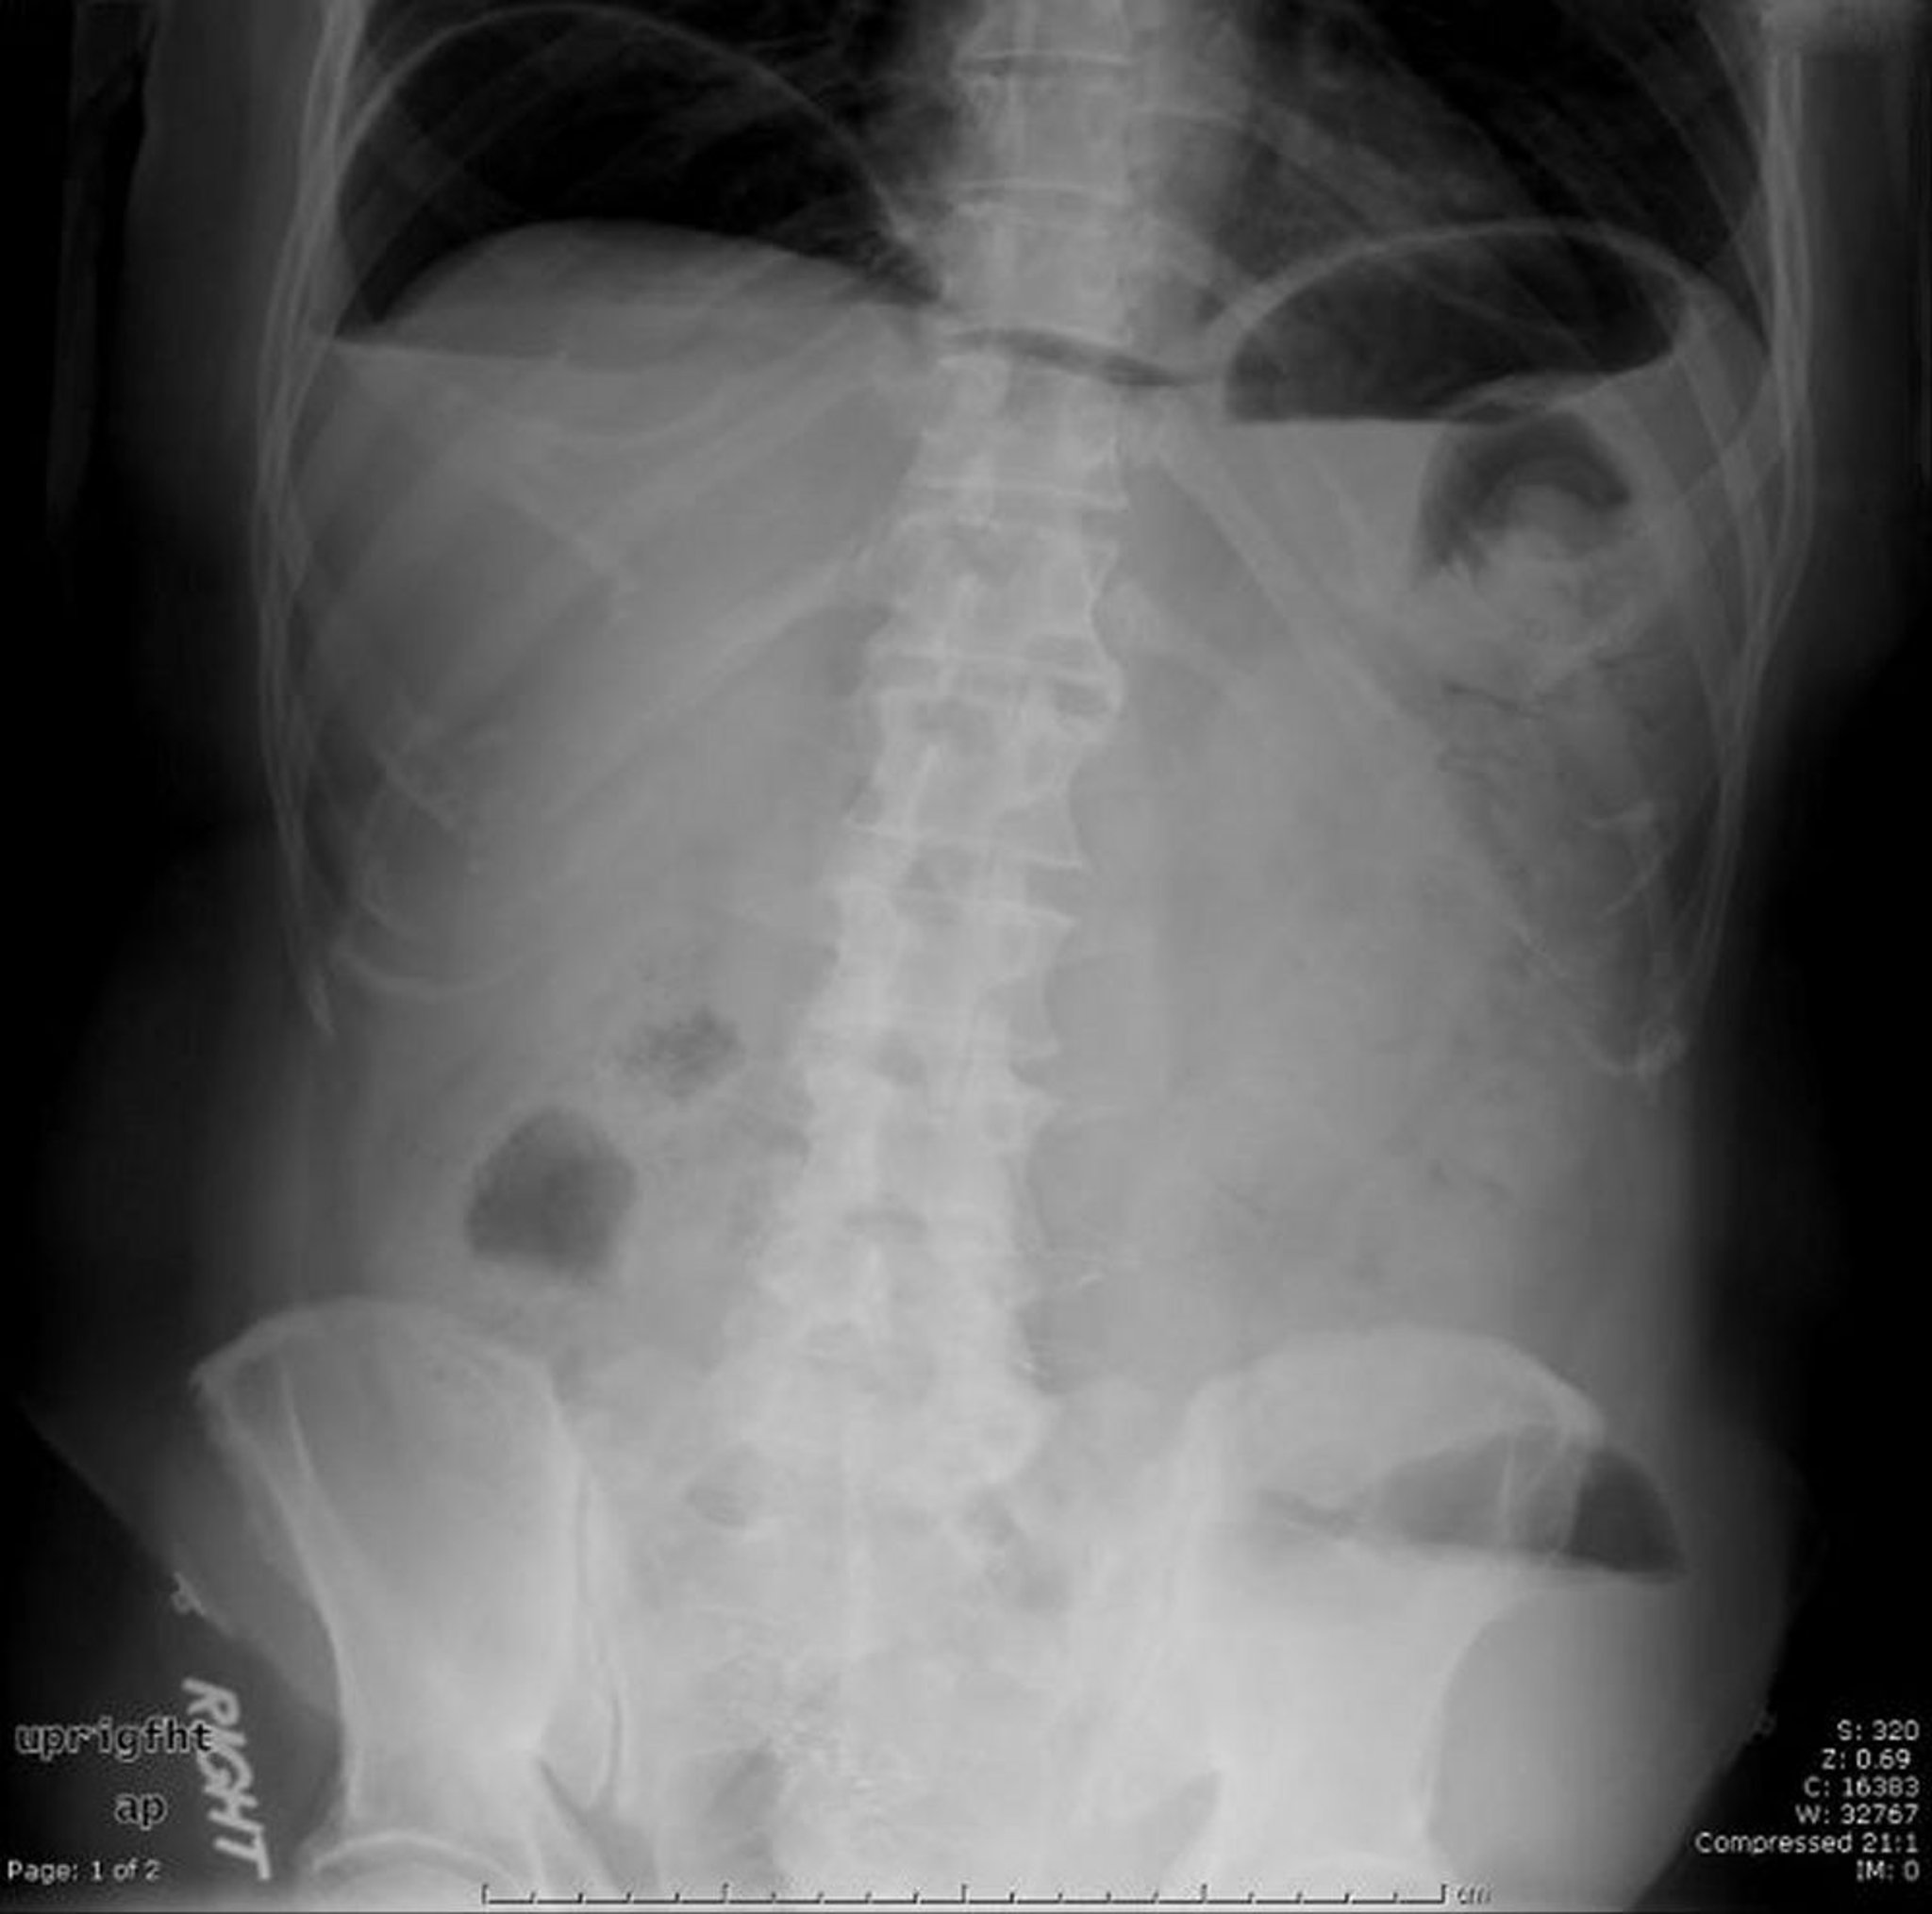

Air libre (pneumopéritoine)

Cette radiographie abdominale montre de l'air libre causé par une perforation.

Image provided by Parswa Ansari, MD.